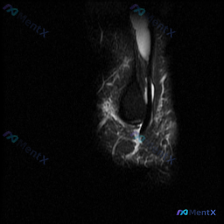

今天碰到一个有意思的病例:临床主诉怀疑肩部软组织有积液,但给到的只有一张肩部MRI T2加权轴位图像,我们一起来整理一下分析思路。 病例核心信息 临床怀疑「肩部软组织积液」,提供单张肩部MRI T2序列轴位图像 - 图像质量:信噪比较低,有一定伪影,主要解剖结构可辨认 - 影像读片结果: 1. 骨骼...